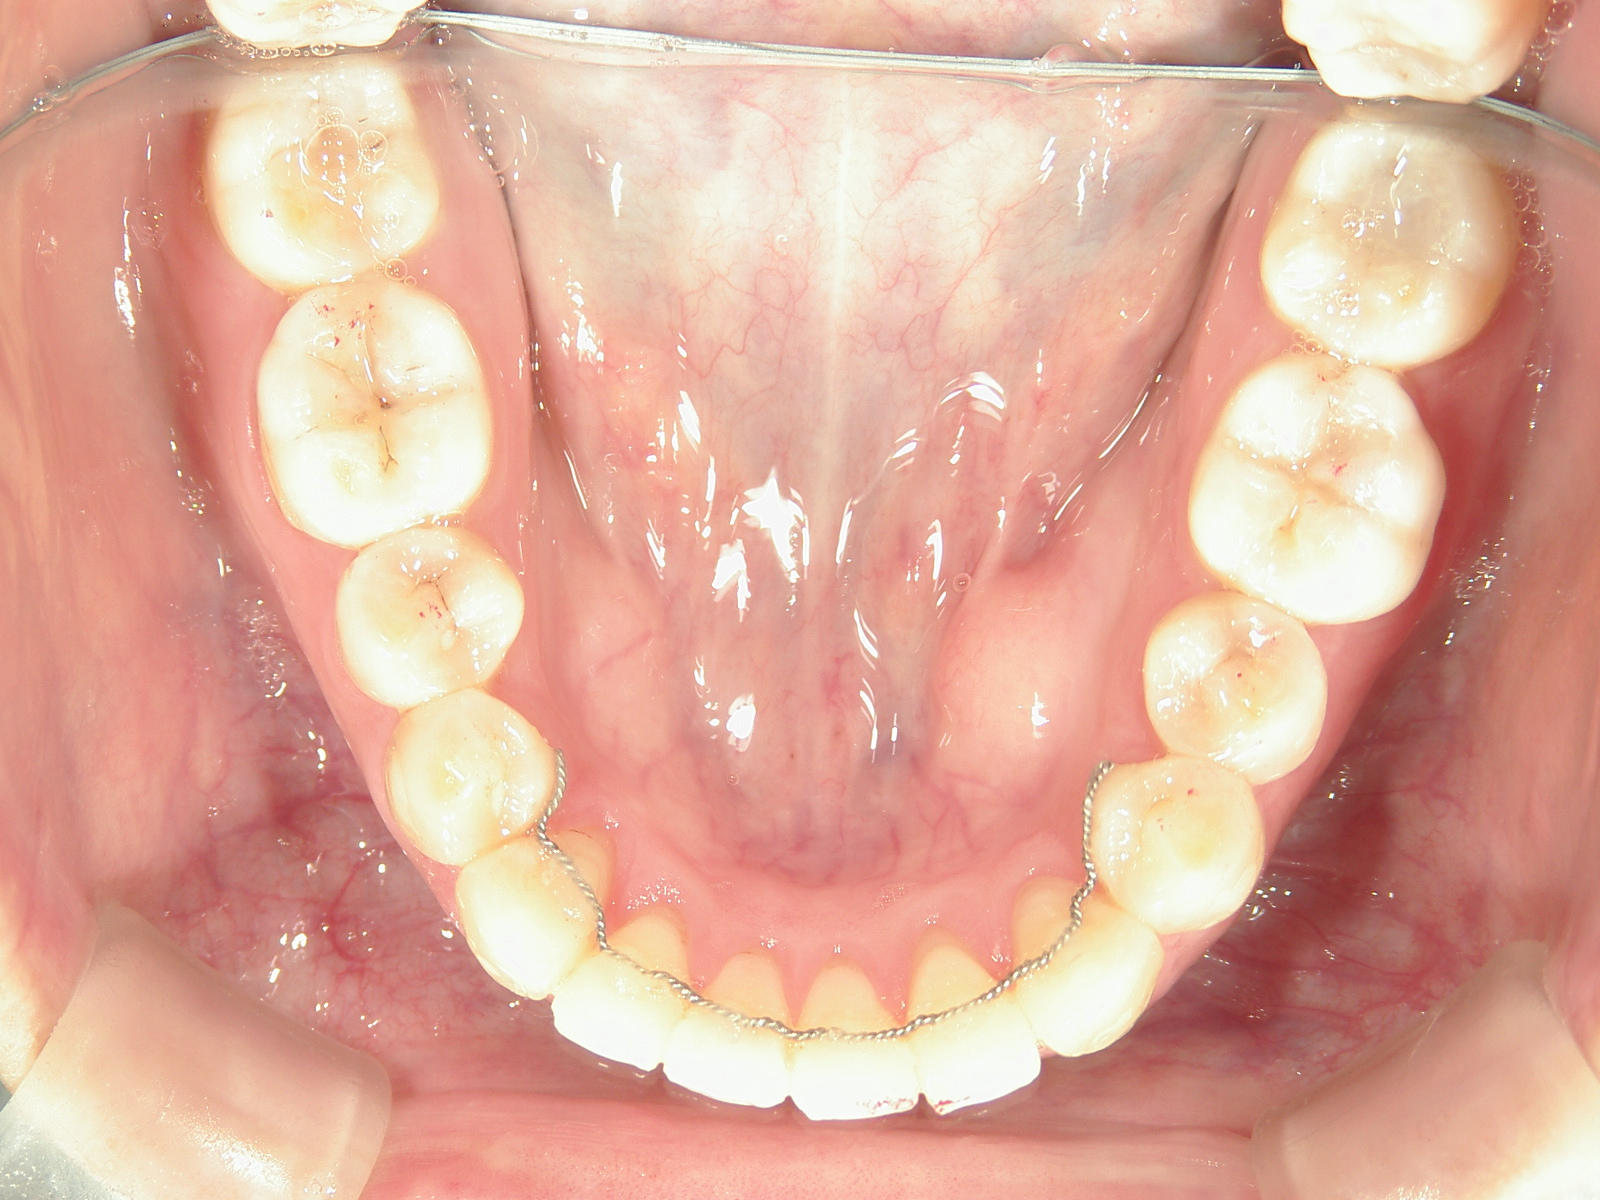

プチワイヤー矯正 症例(53)

スライスカットを併用。

カテゴリー : ガタガタ(叢生)